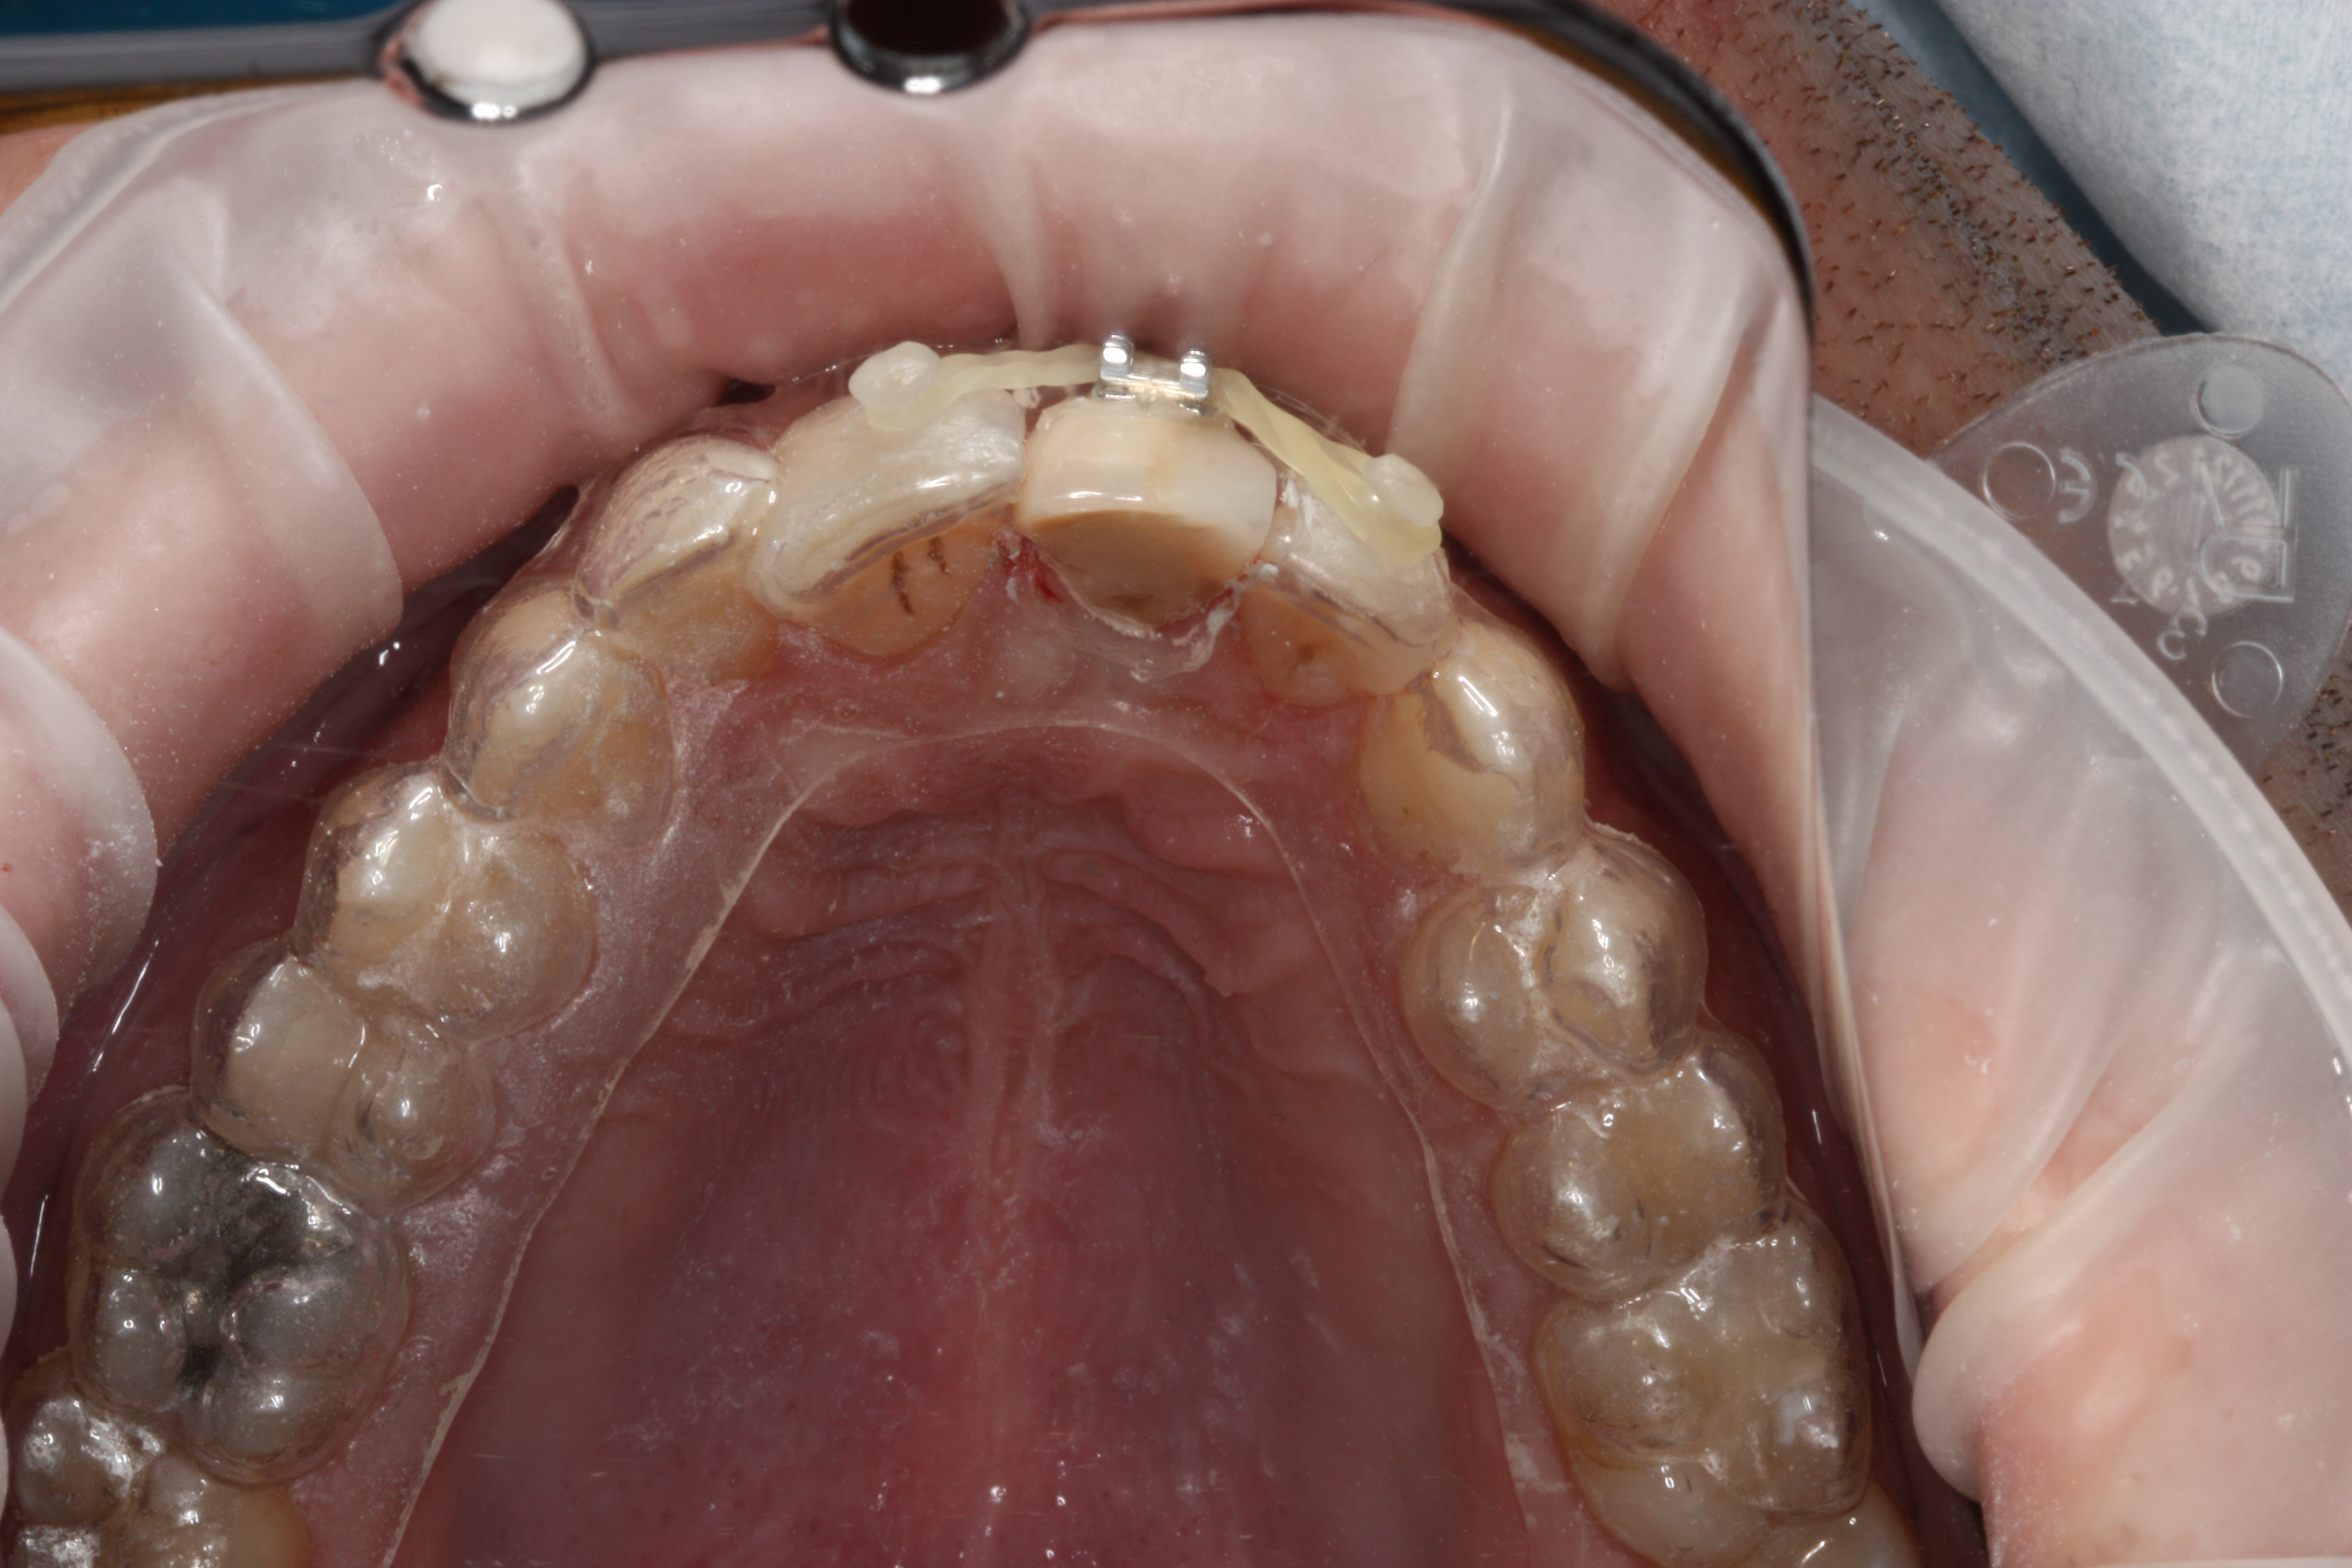

Przykład ekstruzji ortodontycznej za pomocą płytki termoformowalnej i zameczka ortodontycznego: